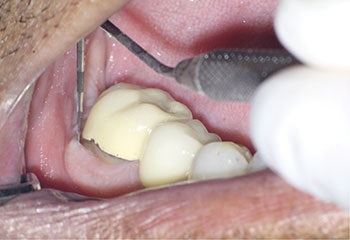

Case 3: A lateral lesion with a superficial crack

This patient presented for a second opinion after an endodontist recommended extraction for tooth #31 because of a VRF on its distal root. A deep isolated probing defect, a cervical sinus tract, the lateral position of the periradicular lesion and the prior placement of a full crown because of cracks in the tooth’s distal enamel marginal ridge likely contributed to the prior diagnosis of VRF.

A new diagnosis of previously treated and chronic apical abscess was made, but the possibility of a VRF was discussed with the patient. RCT was initiated. Internal examination of the pulp chamber reassuringly revealed that a crack on the distal wall of the pulp chamber did not extend to the pulpal floor. Treatment was completed in three visits using a calcium hydroxide intracanal medicament. Treatment and postoperative radiographs revealed a sharp dilaceration of the distal root, likely focusing the bony lesion toward the distal surface, not toward the root apex. Four months later, soft tissue and bony healing were confirmed.

Fig. 11: Preop probe.

Fig. 14: Recall probe.